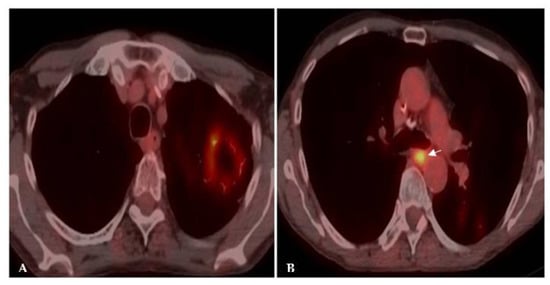

2.1. Lung Nodule or Mass

| Flip-flop node SUVmax > lung mass | Granulomatous Infection | ||||||||

| Lung Nodule or Mass | Non-Resolving Pneumonia | Chronic Cavitating Disease | Disseminated Infection | Bronchiectasis & Asthma | |||||

| Imaging Clue | Dx | Imaging Clue | Dx | Imaging Clue | Dx | Imaging Clue | Dx | Imaging Clue | Dx |

| Adenopathy | Coccidioidomycosis Histoplasmosis | Consolidation + large nodules/masses | Blastomycosis Cryptococcosis Paracoccidioidomycosis | Grape-skin cavities + Lymphadenopathy | Coccidioidomycosis | Miliary ARDS Extrathoracic | ++ Histoplasmosis Coccidioidomycosis | High-attenuation mucus plugging Finger in glove | ABPA |

| Lung Mass | Cryptococcosis Blastomycosis | Adenopathy | Coccidioidomycosis Histoplasmosis | Calcified nodes | Histoplasmosis | ||||